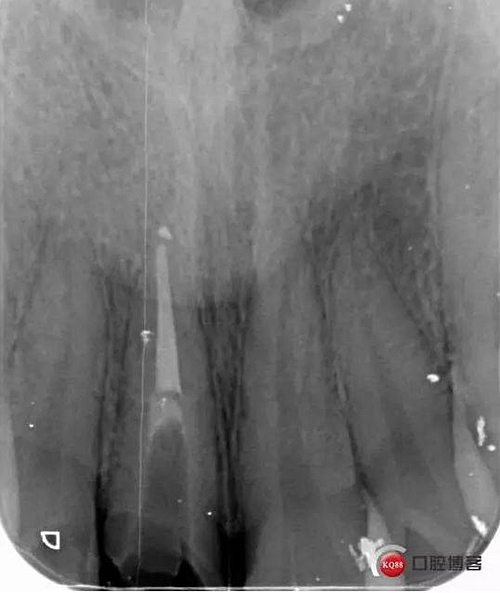

初診檢查:A1殘冠,斷面平齊牙齦,根內(nèi)有繼發(fā)齲。牙齦略紅腫,齦緣高度過低。跟患者溝通方案,患者希望盡量保存患牙

看起來有點(diǎn)頭痛哈,拍片檢查

牙根長度比較號,根充完善。這張片子也可以看出,為什么上次脫落了,樁的深度不夠,而且明顯樁根樁道不匹配,打的樁都沒有到位。